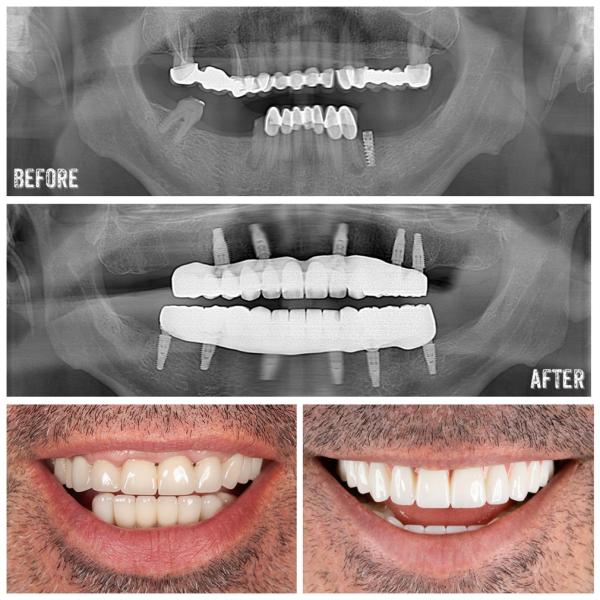

Dental implants in Antalyaare artificial tooth roots made of 100% titanium and placed in the jawbone to restore function and aesthetics of the missing teeth. Titanium is a tissue-friendly material, and dental implants made of titanium are subjected to various procedures such as roughening, covering with different materials, for cellular attachment to the jawbone. After the dental implants are placed in the jawbone, they are held as cellular by creating a special bond with the bone. When this attachment is completed (1-6 months), the denture prosthesis that we call superstructure is ready for preparation. This step is like making a chrono or bridge over a normal cut tooth.

Why Dental Implants in Antalya

Dental implants are the best alternatives for natural teeth today in the case of tooth deficiency. It is the prosthetic rehabilitation method which gives the best result especially when there is no need to support the teeth on the side of the bridge or if there are no teeth to be supported. In addition, it is the most successful method that does not have alternative dental implants for totally fixed prosthesis applications or to increase the retention of total prosthesis in case of total toothlessness.

Application of Dental Implants in Antalya

Dental implants are a longer-lasting treatment than fixed bridges made using removable dentures or adjacent teeth on gums. Dental implants are placed inside the jawbone by our mouth, teeth, jaw surgery specialist.